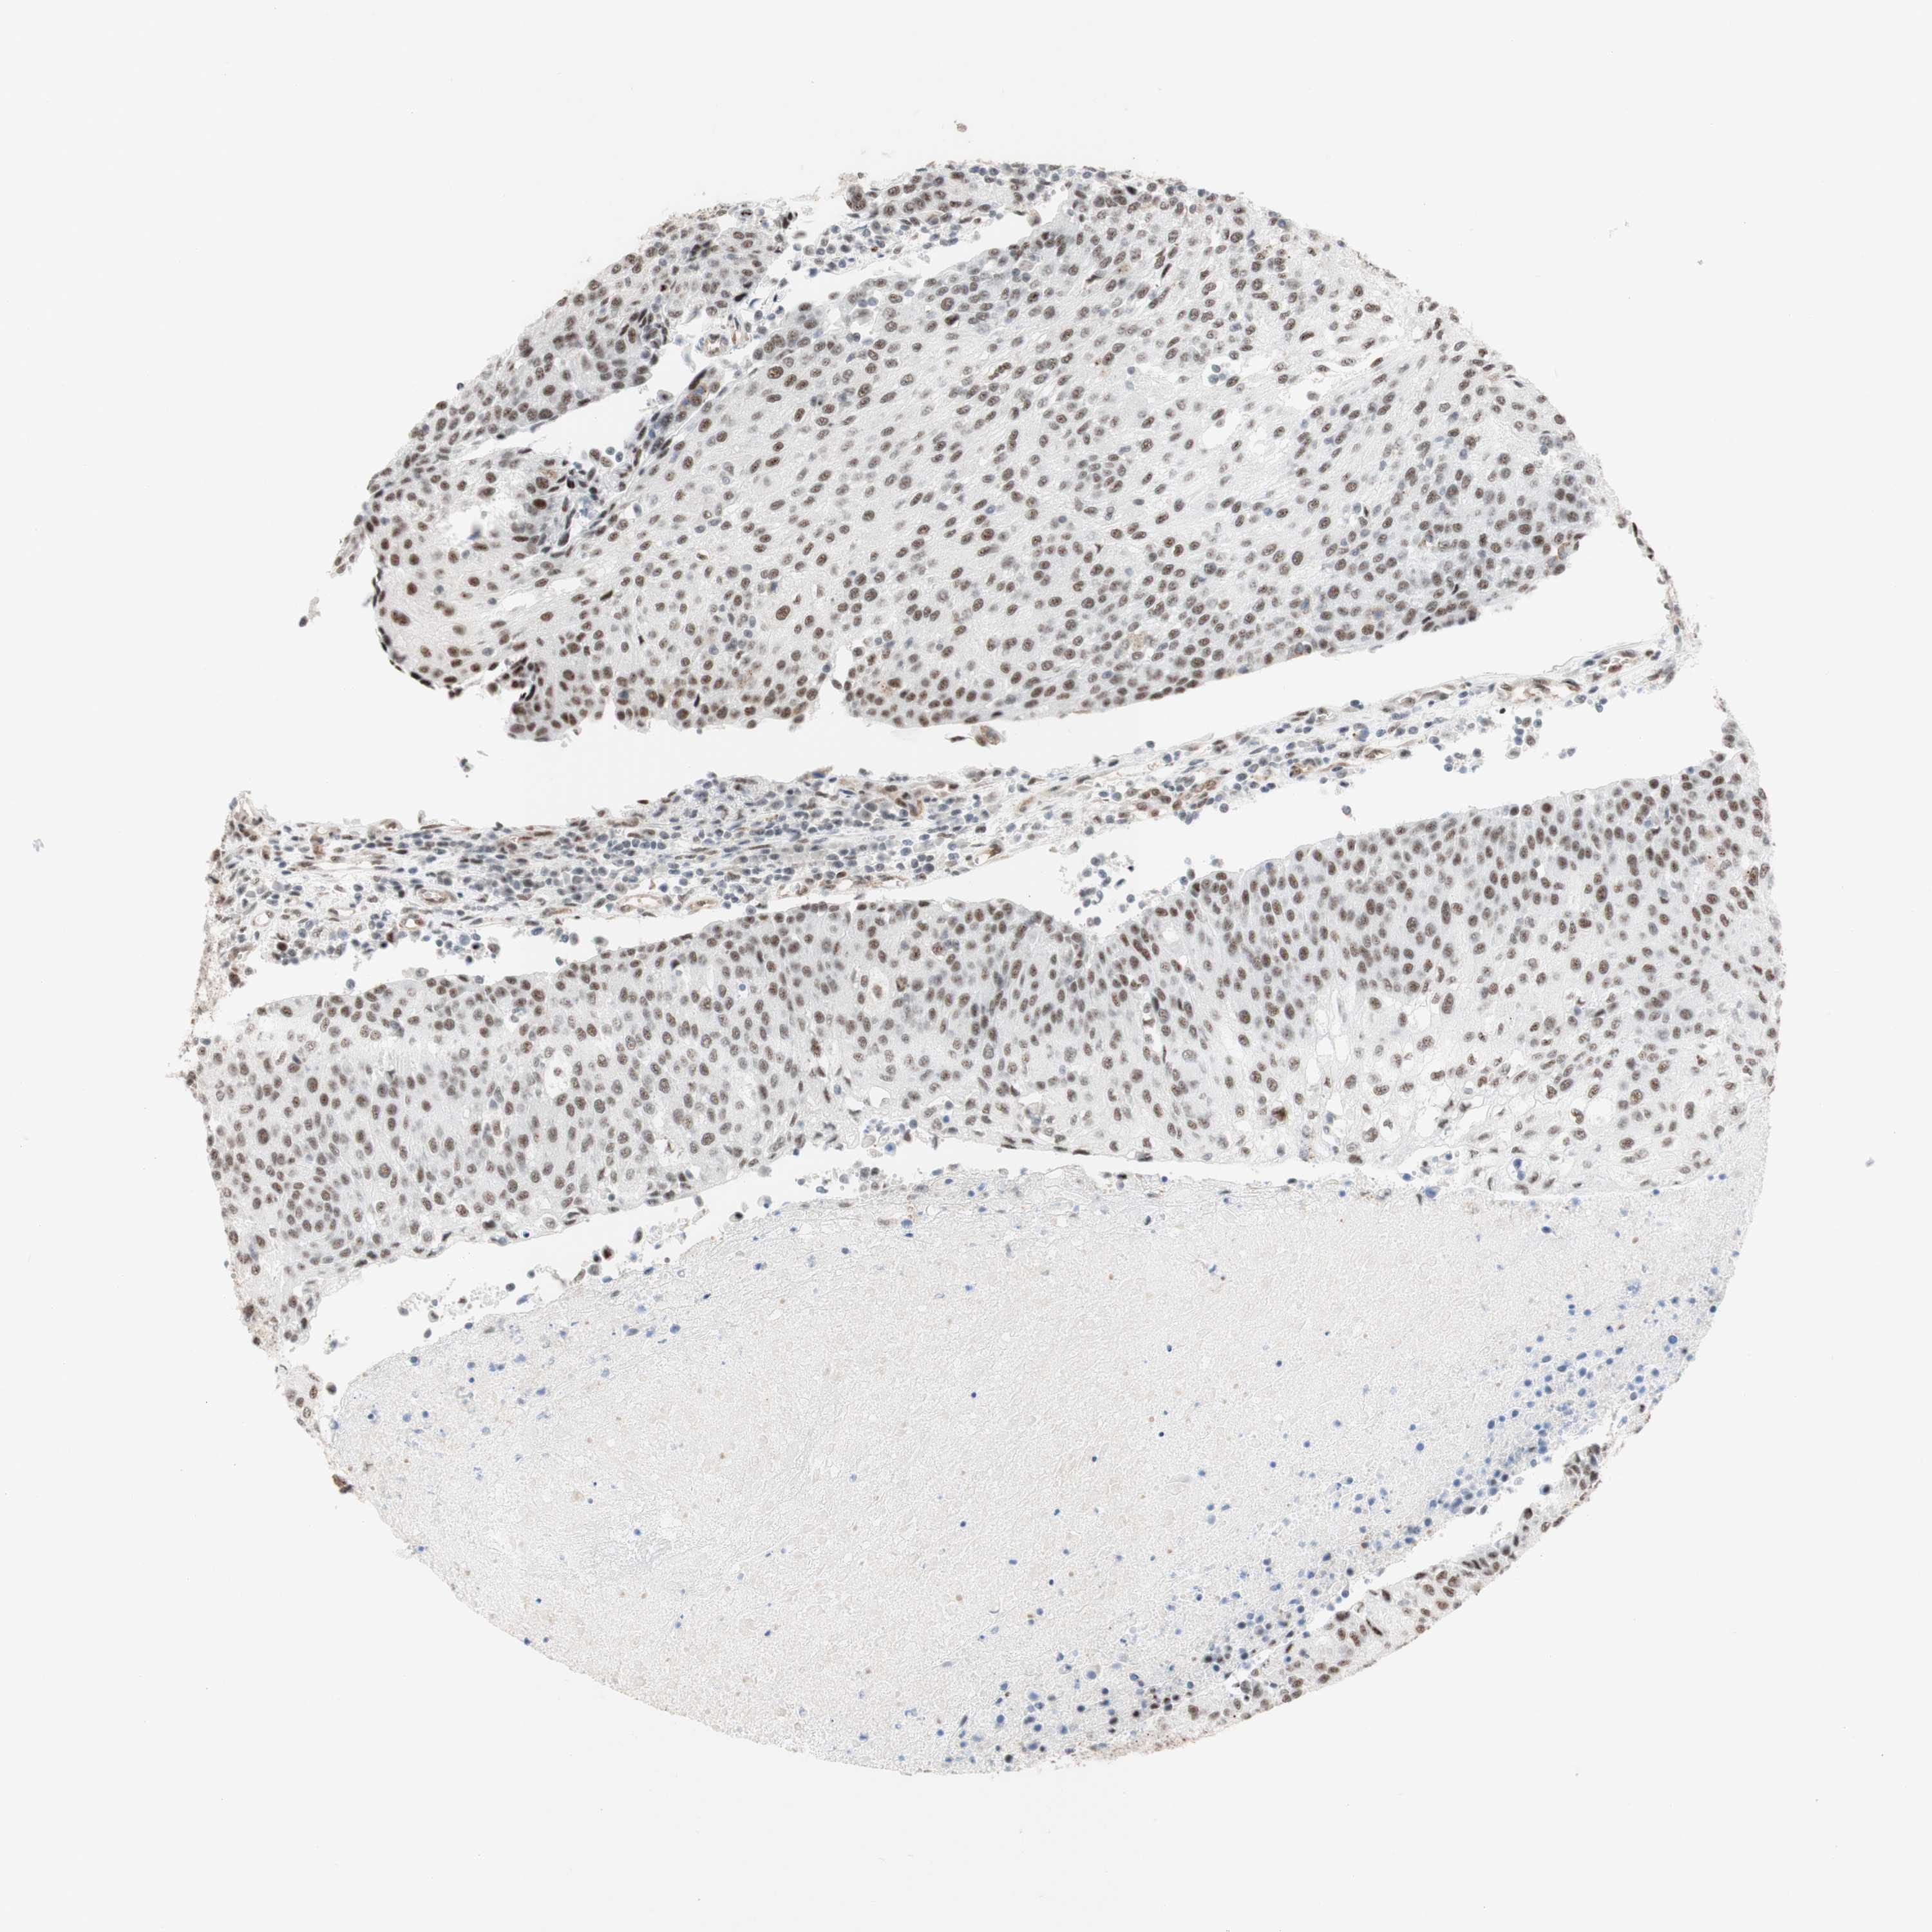

UROTHELIAL CANCER - Protein expressioni

A mouse-over function shows sample information and annotation data. Click on an image to view it in a full screen mode. Samples can be filtered based on level of antibody staining by selecting one or several of the following categories: high, medium, low and not detected. The assay and annotation is described here.

Note that samples used for immunohistochemistry by the Human Protein Atlas do not correspond to samples in the TCGA dataset.

Antibody stainingi

Antibody staining in the annotated cell types in the current human tissue is reported as not detected, low, medium, or high, based on conventional immunohistochemistry profiling in selected tissues. This score is based on the combination of the staining intensity and fraction of stained cells.

Each image is clickable and will lead to virtual microscopy that enables deeper exploration of all samples and also displays staining intensity scores, fraction scores and subcellular localization as well as patient and tissue information for each sample.

Antibody HPA011352

Antibody CAB012273

Staining

High

Medium

Low

Not detected

Intensity

Strong

Moderate

Weak

Negative

Quantity

>75%

75%-25%

<25%

None

Location

Nuclear

Cytoplasmic/membranous

Cytoplasmic/membranous,nuclear

Urothelial carcinoma, Low grade

Urothelial carcinoma, High grade